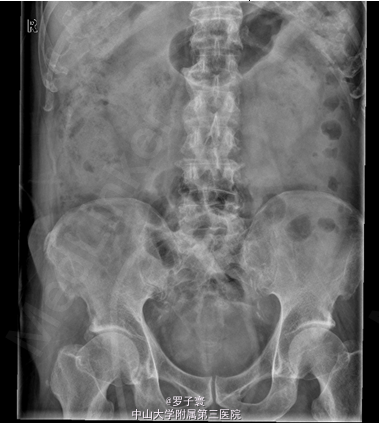

者入院完善相关检查:尿常规提示红细胞计数增高(RBC44个/ul),生化、凝血、术前筛查、肿瘤三项、PSA两项、性激素六项、血常规未见明显异常。泌尿系彩超:双肾集合系统回声增多,不排除小结石;双侧输尿管未见扩张;膀胱多发结石;前列腺增大,前列腺钙化斑;双侧精囊超声检查未见明显异常。腹部平片:考虑膀胱多发结石。

患者排除相关禁忌症于2014-06-04行经尿道膀胱碎石取石术。腰硬麻下,取截石位,手术部位常规消毒铺巾。 F27经皮肾镜连接监视系统,直视下进入膀胱,见后尿道前列腺中度增生,膀胱颈明显抬高,膀胱内小梁小房,可见憩室,见黄褐色膀胱结石5个,约2.1×1.2cm,表面粗糙,不规则形,褐色,双侧输尿管开口无水肿、狭窄等,接超声碎石系统,经皮肾镜进入膀胱,击碎结石,将碎石吸出,收集碎石送检,手术过程顺利,术中出血少,未输血,术后病人安返病房。术后予抗生素预防感染、补液等对症治疗,于2014-06-07拔除尿管。